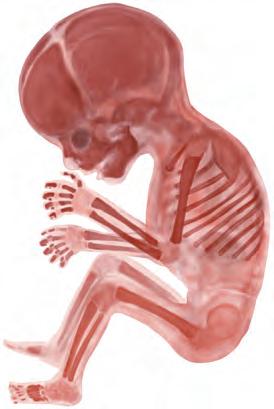

13a-16a settimana Tale periodo è caratterizzato da un accrescimento estremamente rapido del tronco, del collo e degli arti. La testa si solleva. Il corpo si copre di sottili peli, la lanugine, e il tipo di capigliatura diventa riconoscibile. L’ossificazione procede, cosicché nel feto di 16 settimane (B) le ossa sono riconoscibili in radiografia.

B Feto, 16a settimana, sviluppo dello scheletro, rosso alizarina